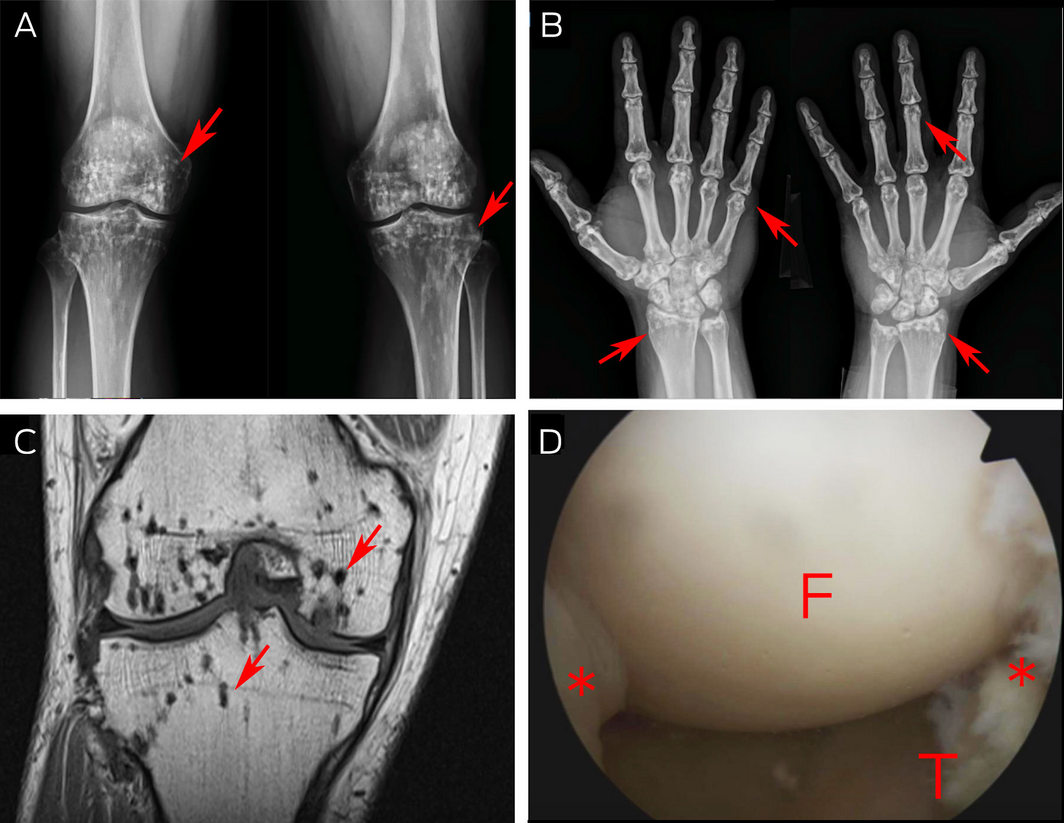

- 1. Woyciechowsky TG, Monticielo MR, Keiserman B, Monticielo OA. Osteopoikilosis: what does the rheumatologist must know about it? Clin Rheumatol 2012; 31: 745‐748.

- 2. Hellemans J, Preobrazhenska O, Willaert A, et al. Loss‐of‐function mutations in LEMD3 result in osteopoikilosis, Buschke–Ollendorff syndrome and melorheostosis. Nat Genet 2004; 36: 1213‐1218.

- 3. Negi RS, Manchanda KL, Sanga S, et al. Osteopoikilosis — spotted bone disease. Med J Armed Forces India 2013; 69: 196‐198.

- 4. Mahbouba J, Mondher G, Amira M, et al. Osteopoikilosis: a rare cause of bone pain. Caspian J Intern Med 2015; 6: 177‐179.